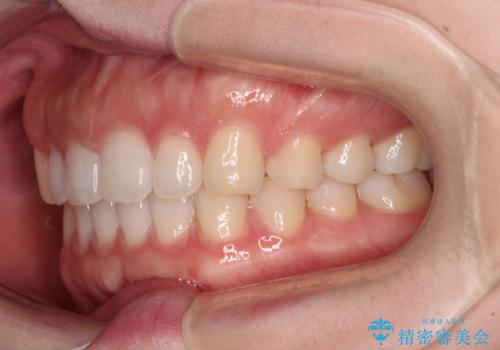

すきっ歯とオープンバイト インビザライン・ライトで改善

- 食いしばりによる顎の負担を気にして来院された患者様です。

当初は、ボツリヌス毒素による咬筋の過緊張の緩和と、睡眠時のマウスピース装着による咬合負担の解消を行いました。

オープンバイトのため、奥歯に負担のかかる咬合状態であったので、矯正治療を提案したところ、希望をされました。

すきっ歯程度の軽度の歯列不正であったため、インビザライン・ライトにより咬合改善を行うこととしました。

オープンバイトやすきっ歯は、舌突出癖によりあっという間に後戻りをするため、矯正治療前からトレーニングを行っていただき、更には後戻り防止のワイヤーリテーナーを併用しています。